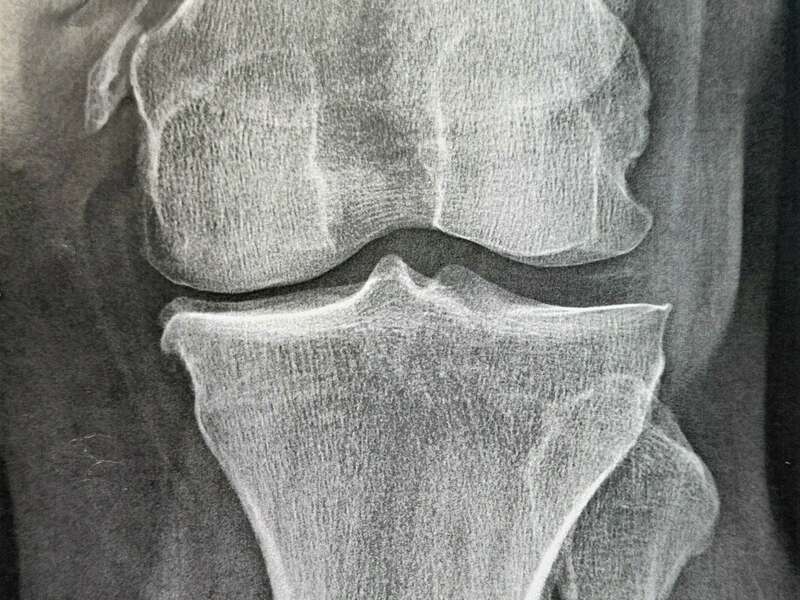

L’articulation du genou assure la jonction entre le fémur (condyles fémoraux), le plateau tibial et la rotule (patella). Elle se compose de deux articulations : l’articulation fémoro-patellaire entre le fémur et la rotule et l’articulation fémoro-tibiale qui elle-même se divise en deux compartiments (interne et externe).

L’ensemble des zones de frottement entre les différents os est recouvert d’un cartilage d’une épaisseur d’environ 3 à 4 mm d’épaisseur qui facilite le glissement entre les différentes surfaces articulaires.

Elle sera confirmée par des examens radiologiques tels que des radiographies du genou. En cas de doute diagnostic ou afin de rechercher d’éventuelles lésions associées, un scanner et/ou une IRM pourront être prescrits.